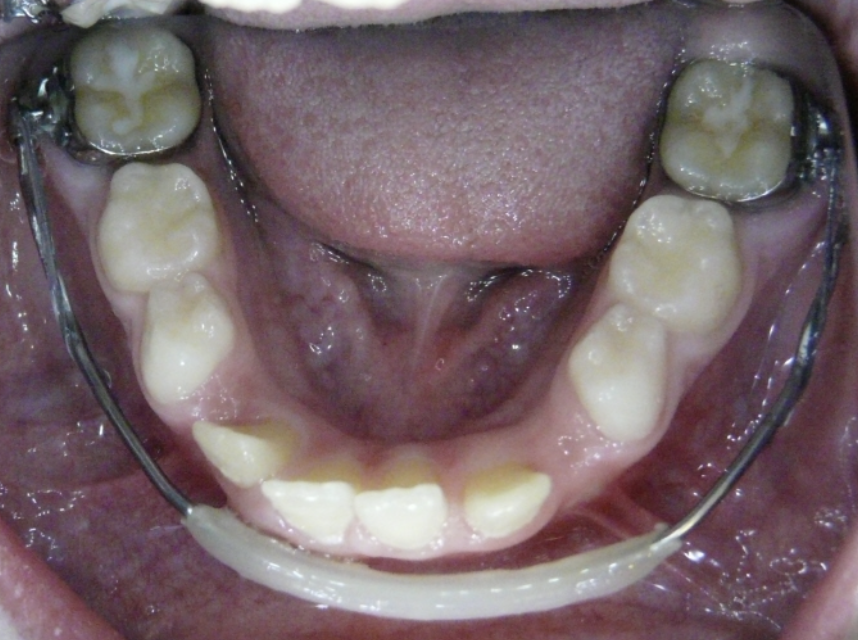

Posterior Crossbite

Top teeth are inside of bottom teeth.